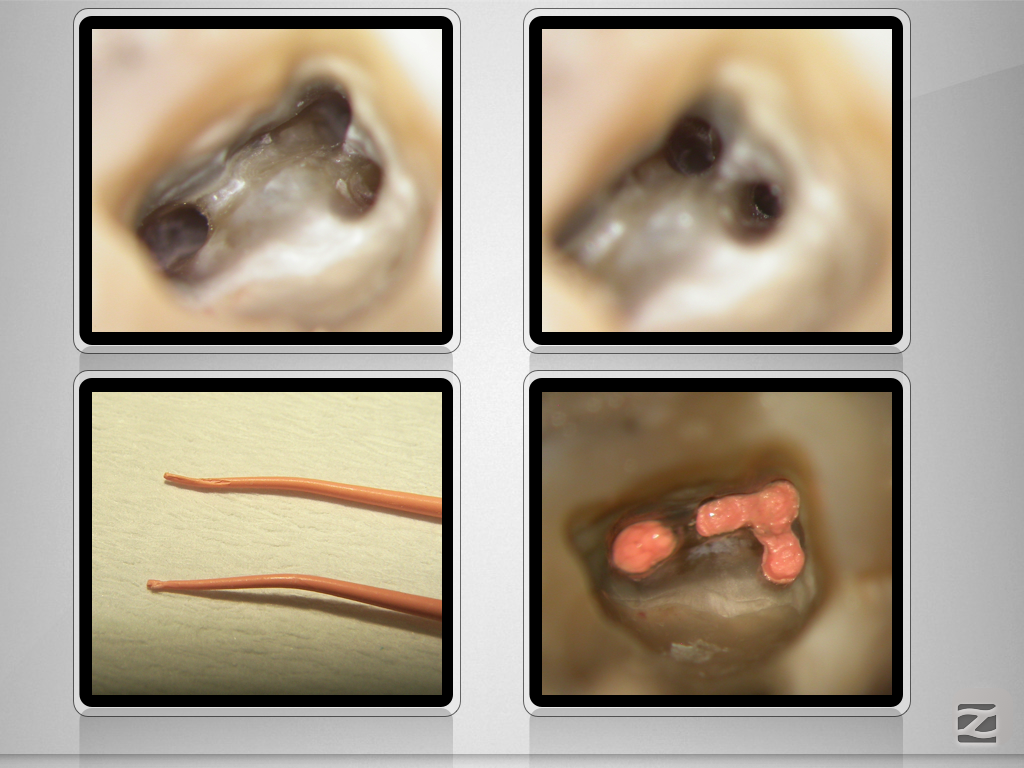

Gewusst, wo’s lang geht.